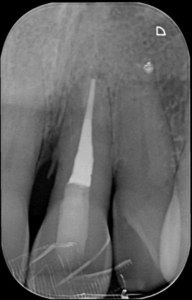

Het beeld op de röntgen opnames leek overeen te komen met de verschijnselen behorende bij een endo/paro probleem, veroorzaakt door een lateraal kanaal.

De aanwezige kanaalbehandeling leek lege artis uitgevoerd hoewel de kanaalpreparatie niet centraal in het element kon worden gehouden. Aan de mesiale zijde was de wand dunner dan aan de distale zijde. Dat kon te maken hebben met de problemen die de vorige clinicus ondervond bij het zoeken naar een waarschijnlijk geoblitereerd kanaal. Ook vonden we de preparatie fractioneel te kort.

Afbeeldingen 1 (2) t/m 10(2) geven een beeld van element 36 waar wel op tijd de juiste diagnose werd gesteld. De eindfoto’s laten een fraai lateraal kanaal zien dat zorgde voor het interradiculair botverlies en de bijbehorende pocket van 10+ millimeters. Na 6 maanden is het defect volledig genezen.

Obturatie door middel van het lateraal en koud condenseren van gutta percha leidt zelden of nooit tot het obtureren van laterale anatomie, dus zeker in dit soort gevallen waar we laterale anatomie vermoeden zou de eerste keuze altijd moeten zijn om vertikaal en warm gutta percha te condenseren.

We beginnen de obturatie nadat de spoelsessies zijn gedaan. NaOHCl 5.5% als laatste spoelgang en enkele malen afgewisseld met 17% EDTA.

Controle

Vol verwachting maken we de eindfoto’s en helaas: geen spoor van laterale anatomie te bespeuren.